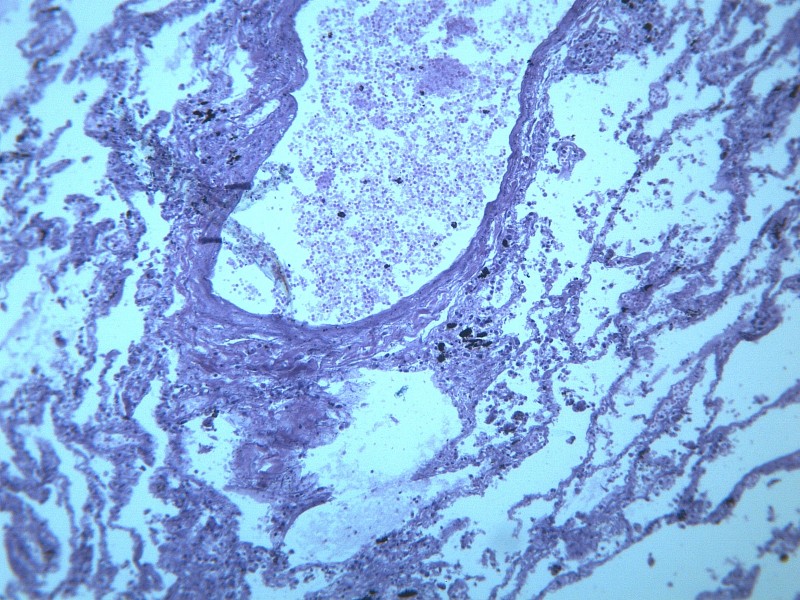

慢性支气管炎(chronic bronchitis)是由于感染或非感染因素引起气管、支气管粘膜及其周围组织的慢性非特异性炎症。其病理特点是支气管腺体增生、粘液分泌增多。临床出现有连续两年以上,每持续三个月以上的咳嗽、咳痰或气喘等症状。早期症状轻微,多在冬季发作,春暖后缓解;晚期炎症加重,症状长年存在,不分季节。疾病进展又可并发阻塞性肺气肿、肺源性心脏病,严重影响劳动力和健康。